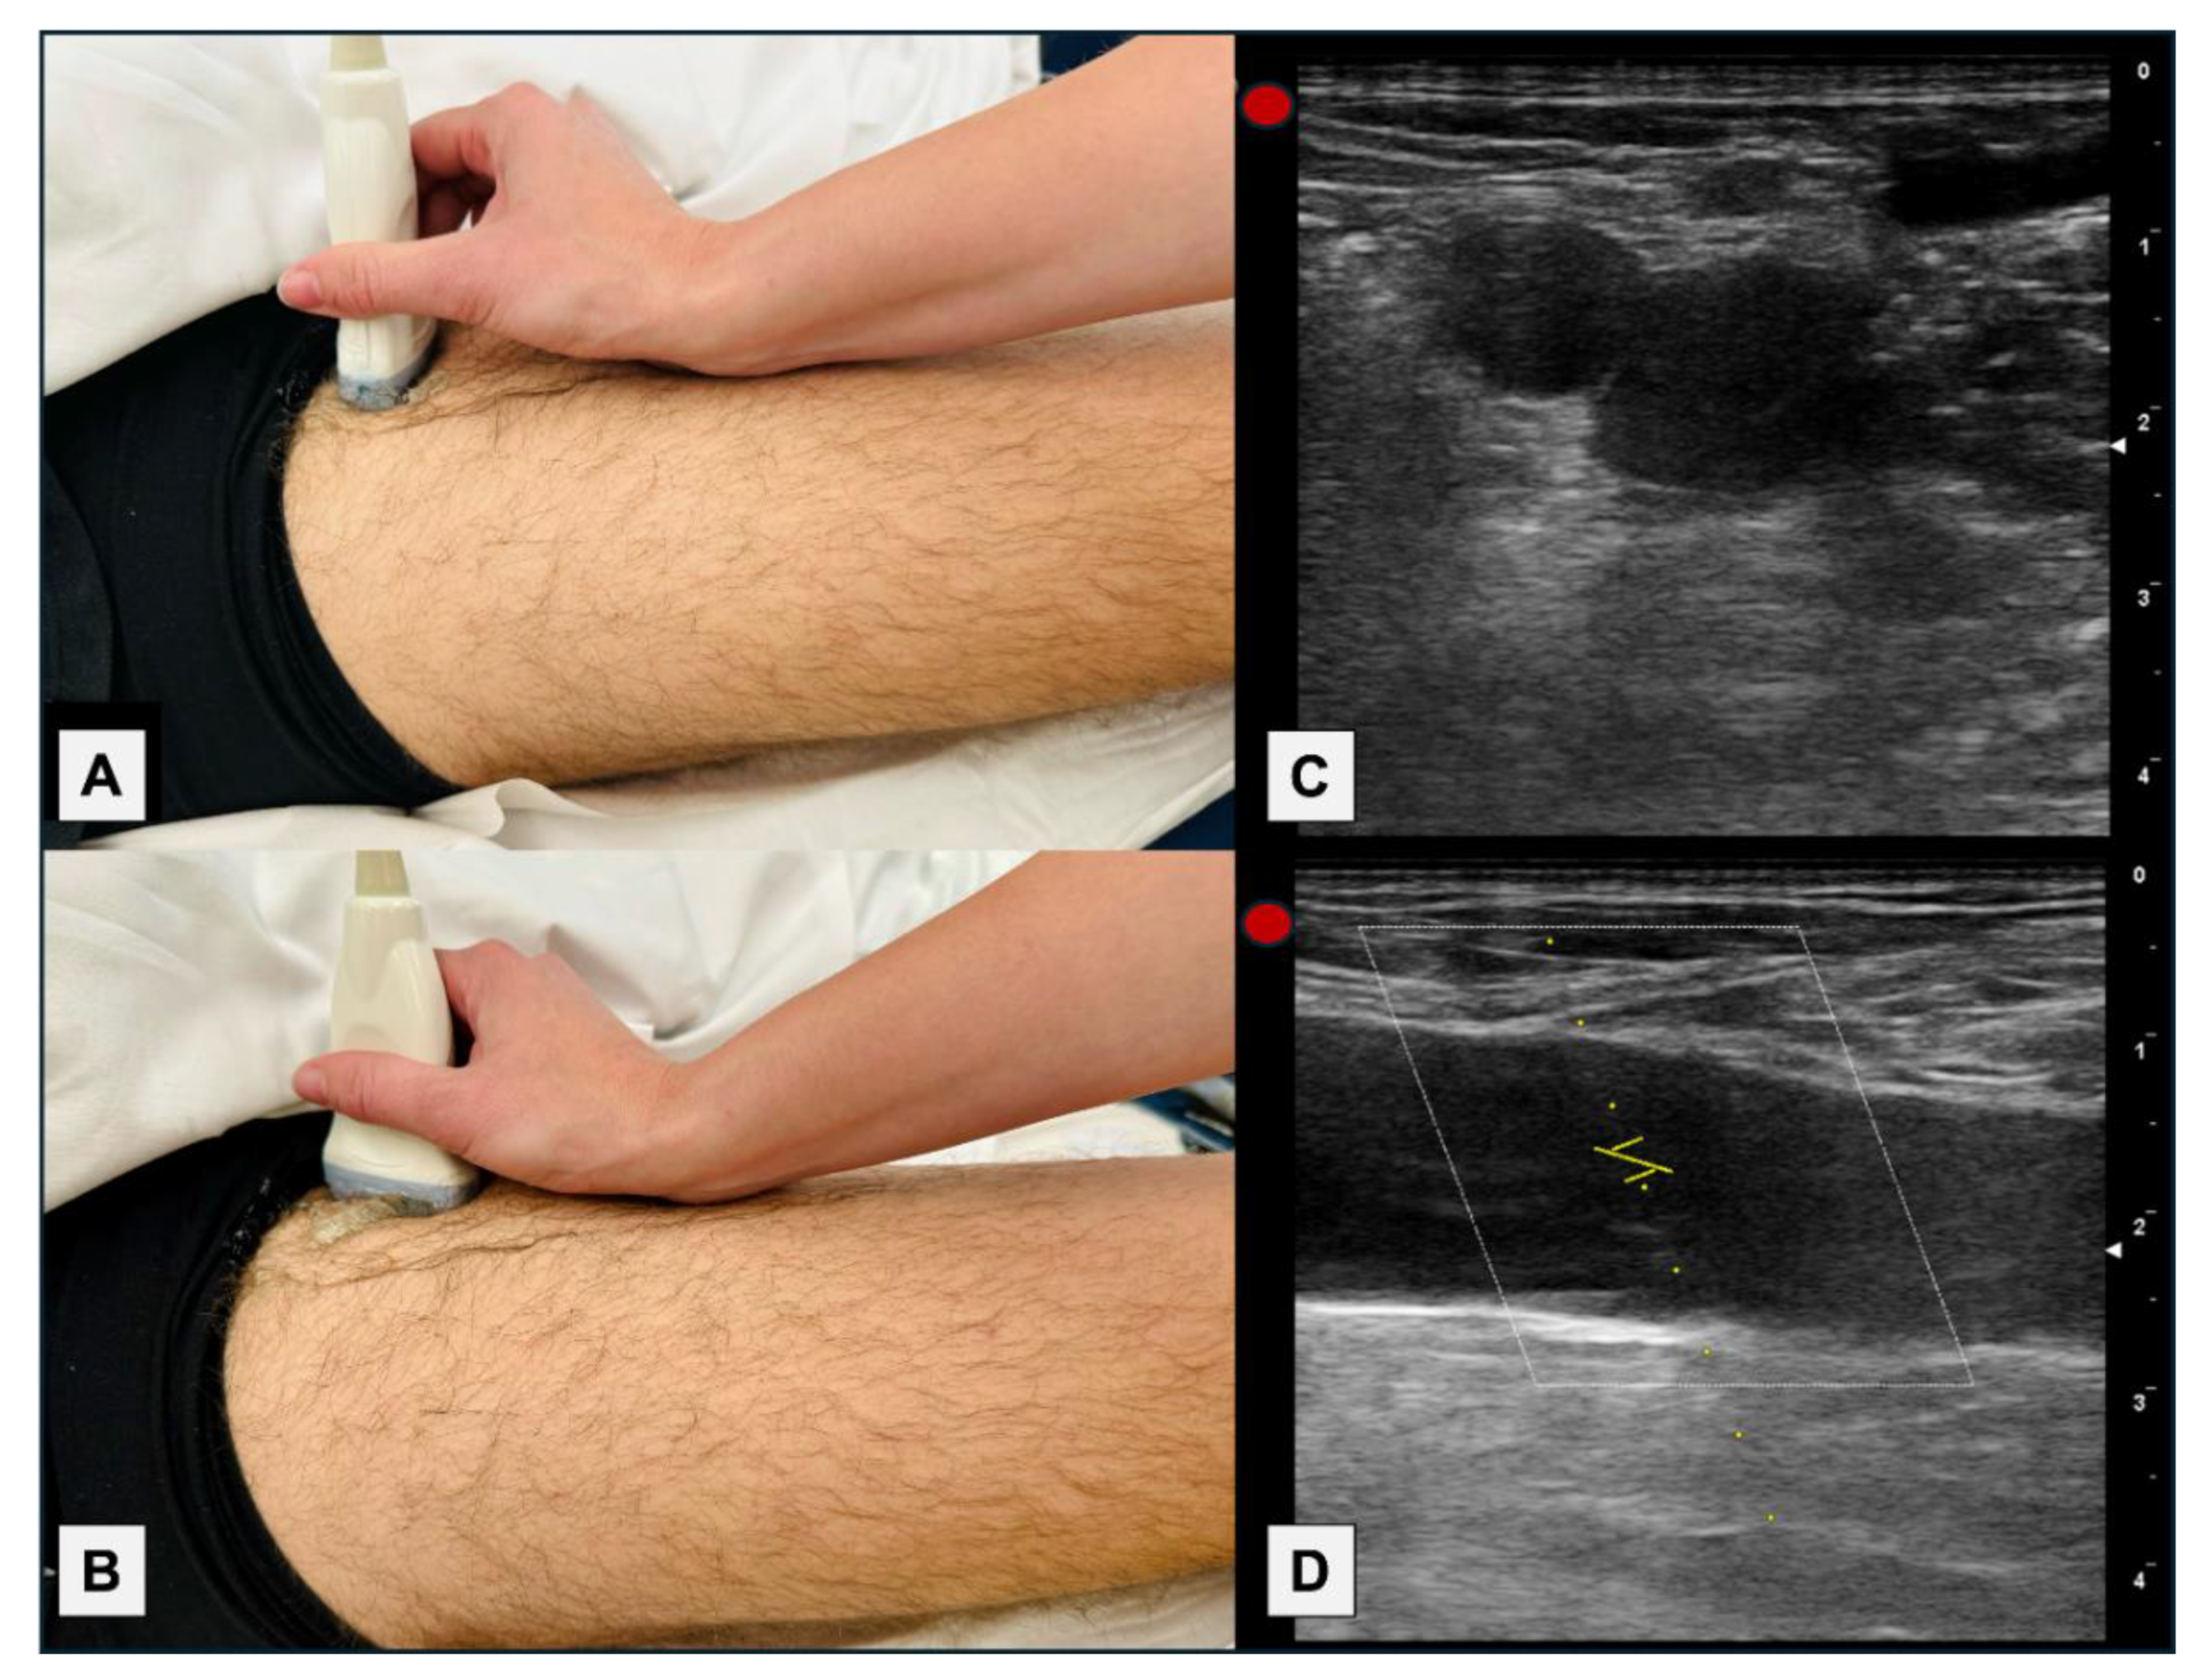

This was a prospective, multicenter observational study conducted in three hospitals. Due to the limited existing evidence regarding the assessment of CFV by PW-Doppler, the study was considered a pilot study, and a calculation of the necessary number of patients was not performed as such. A complete echocardiography was performed, which included all the parameters mentioned for calculating PHP (Figure 1). The morphology of the PW-Doppler of the CFV was assessed using a linear probe, in a supine position, proximally to the saphenous vein, after confirming the absence of deep vein thrombosis, in a longitudinal plane, and adjusting the scale to +20/-20 cm/s (Figure 1 and Figure 2).

Another issue we considered was whether to perform measurements in the longitudinal or transverse plane. Although the transverse plane would have been simpler, and we probably would have obtained the same results (considering that the scale should be increased, as the speeds are lower), we chose to evaluate the longitudinal plane of the CFV, because all studies conducted to date used that plane, including ours. A technical issue is that when evaluated in the longitudinal plane and with the flow perpendicular to the PW-Doppler insonation, it is necessary to perform an angle adjustment for a more adequate evaluation (Figure 3). A specific study comparing the transverse and longitudinal planes would be needed to establish their equivalence and further increase the simplicity and speed of the examination.

Other technical considerations to consider are to rule out the presence of deep venous thrombosis through compression, and the supine position, as it can affect the pattern of the PW-Doppler by compressing the own abdomen compressing the CFV in a seated position, or by increasing the return if the legs are elevated. We must not forget to adjust the scale to +20/-20 cm/s, because if not, we might not distinguish the cardiac waves.

Figure 2. (A) Probe´s position on the patient for transverse section. (B) Probe´s position on the patient for longitudinal section. (C) Ultrasound image of the transverse section at the level of the CFV. (D) Ultrasound image of the longitudinal section of the right CFV. In this case, the cranial region is on the left (transducer mark) and the caudal region is on the right of the image.